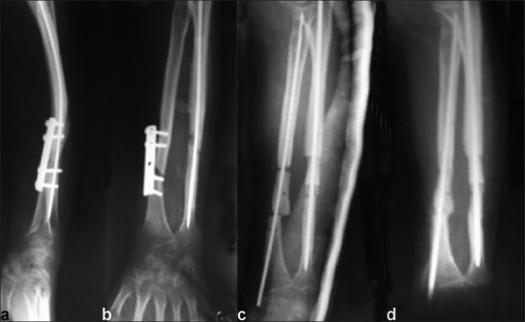

The management of an atrophic nonunion with a gap following a fracture of the radius and/or ulna is a challenging problem. Various methods of treatment available in the literature are cortical tibial graft (Boyd), ulnar segment graft (Miller and Phalen), iliac crest graft (Spira), cancellous insert graft (Nicoll), vascularized fibular graft (Jupiter), and bone transport by ring fixator (Tesworth). The present study reports the results of tricorticocancellous bone block grafts using modified Nicoll's technique, in diaphyseal defects of forearm bones.

MATERIALS AND METHODS

A total of 38 forearm bones (either radius or ulna or both) in 23 patients with a gap of 1.5-7.5 cm were treated by debridement and tricorticocancellous bone block graft under compression with intramedullary nail fixation between June 1985 and June 2005. There were 15 male and 8 female patients. Sixteen patients had open and seven patients had closed fractures initially. Time of presentation since the original injury varied from 9 months to 84 months. Eighteen patients had already undergone one to three operations.

RESULTS

Thirty-six bones showed union at both host graft junctions. The mean duration of union was 17.5 weeks (range, 14-60 weeks). Two bones had union only at one host graft junction and did not show any evidence of callus formation up to 9 months on the other end, hence requiring subsequent procedure in the form of phemister bone grafting. Patients were followed for a minimum period of 2 years (range, 2-7 years). Results were based on the status of union and range of motion (ROM) for elbow/wrist and grip strength at the final follow-up. Complications observed were the reactivation of infection (n = 1) and herniation of the muscles at the donor site (n = 1).

CONCLUSION

The tricorticocancellous strut bone grafting under optimal compression, augmented with intramedullary fixation, provides a promising solution to difficult problem of an atrophic nonunion of forearms bones with gap.